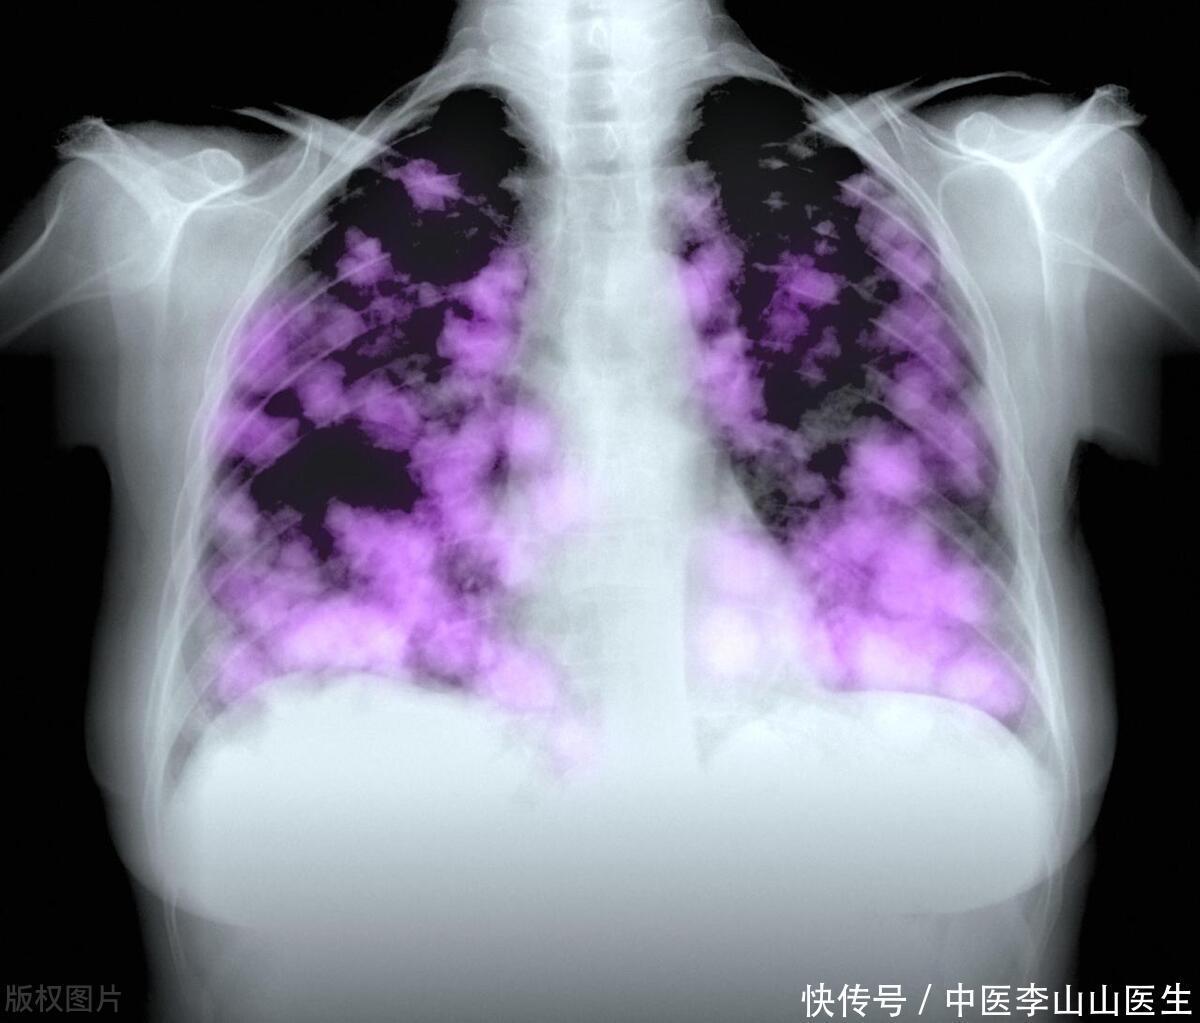

长期抽烟的人,最怕这4种异样!一旦出现,或许离肺癌不远了

肺癌

吸烟

癌细胞